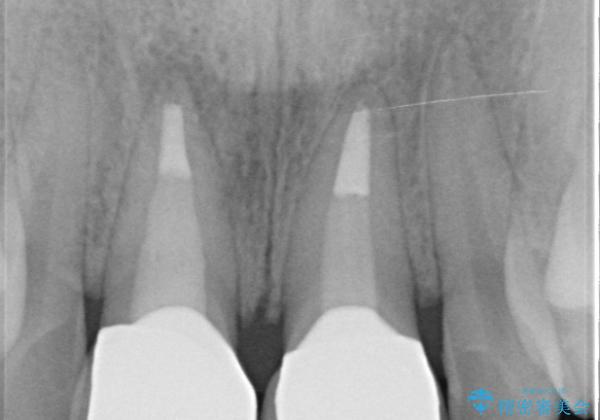

- 3週間後に迫った結婚式までになんとか前歯をきれいにしたいという希望で来院されました。

一回の治療時間を長く取り、限られた時間で最大限の結果を出せるよう集中治療を計画します。

ただ見えるクラウンを白くきれいにするのではなく、長期的な歯の予後を考えると根管治療・ファイバーコア築盛・精密な歯牙形成等クリアすべき条件は多々あると言えます。